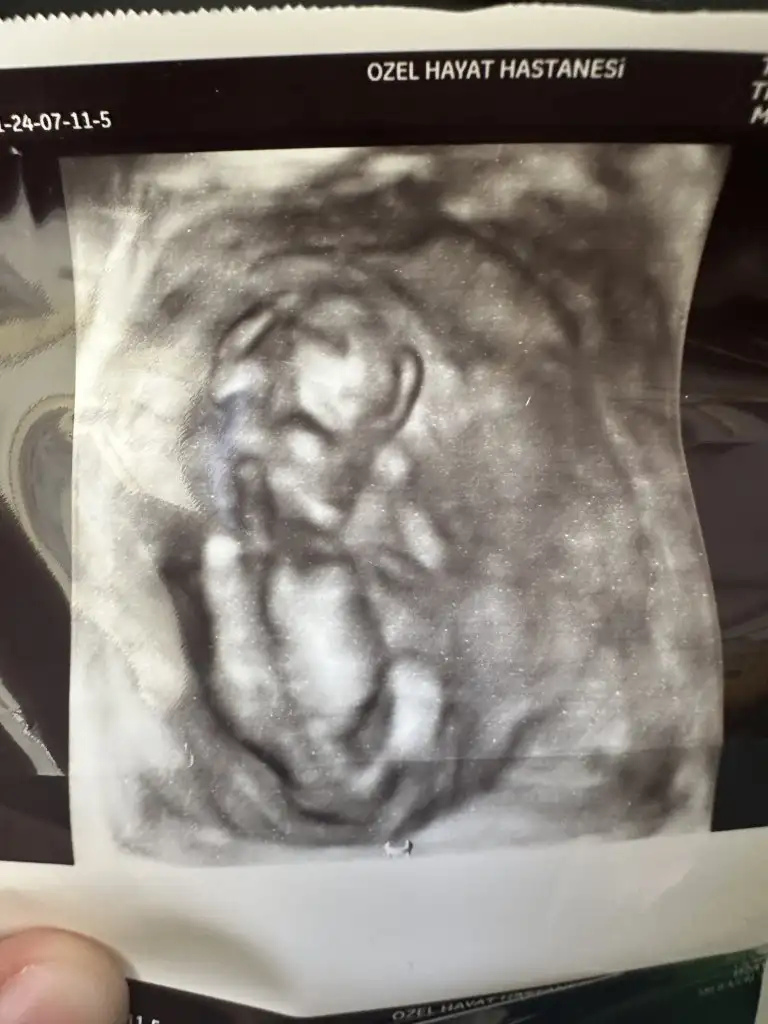

Merhaba bende yorum istiyorum 12 haftalık bebeğim